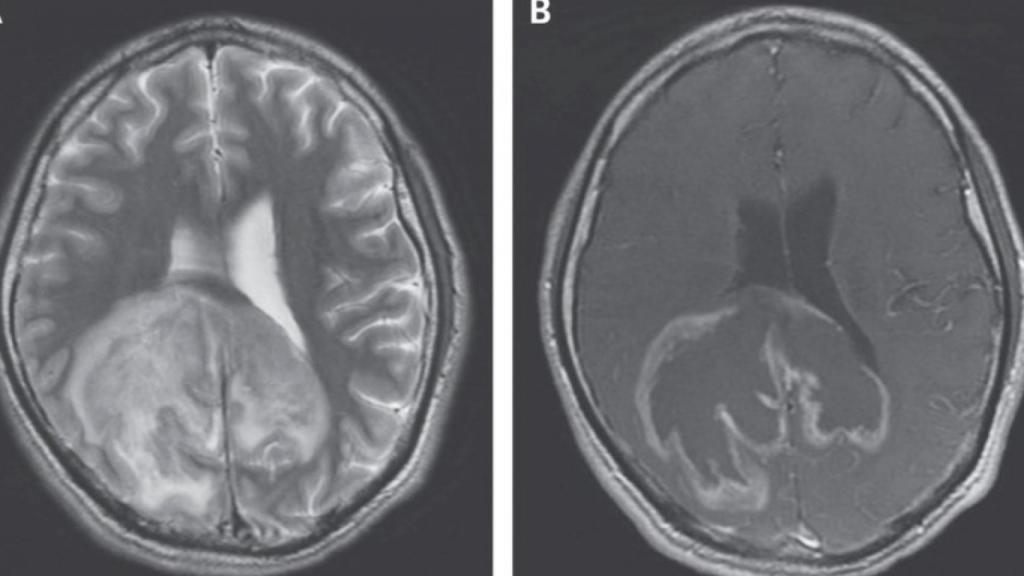

Según los autores del caso, pertenecientes a la Universidad de Stanford, al paciente se le realizó una resonancia magnética. En dicha prueba de imagen se visualizó la enorme masa cerebral, de un considerable tamaño. Asimismo, también se analizó su líquido cefalorraquídeo -la sustancia que recorre, protege y nutre al sistema nervioso central-, detectando mediante un estudio por microscopio docenas de microorganismos. Teóricamente, este líquido cerebral debe ser estéril.

Mediante el uso de una secuenciación genética de los microorganismos, se llegó a la conclusión de que el causante de la masa cerebral era un parásito llamado Trypanosoma cruzi, un tipo de microorganismo cuyas zonas de mayor actividad son precisamente algunos países de América Latina, donde causan la denominada Enfermedad de Chagas, la cual puede llegar a afectar al músculo cardíaco y ser mortal en algunos casos si no se trata a tiempo.

En raras ocasiones, la enfermedad de Chagas puede afectar al sistema nervioso y causar problemas cerebrales, como fue el caso. De hecho, sufrir SIDA o cualquier otra enfermedad que debilite el sistema inmune puede aumentar el riesgo de "reactivación" del parásito, dando lugar a abscesos o masas cerebrales, las cuales son realmente colecciones de pus debido a la infección parasitaria, aunque pueden ocasionar síntomas similares a un tumor cerebral debido al efecto de compresión que causan en las diferentes estructuras del cerebro.